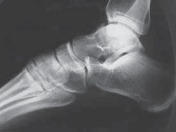

Fractures of the neck of the talus are defined as fractures anterior to the lateral process of the talus. Hawkins’ work on vertical fractures of the neck of the talus helped clarify injury of vascular perfusion to the bone by delineating three types of fractures of the neck of the talus.

1.

The type I fracture is nondisplaced. Disruption of blood flow is limited to the anterolateral region of the bone. I recommend a computed tomography (CT) scan to confirm no displacement of the fracture before diagnosing a type I fracture. Historically, Hawkins reported a 13% incidence of osteonecrosis in type I injuries ( FIG 1A).

2.

In the type II talar neck fracture there is displacement of the talar dome fragment, which is routinely posterior, often depicting clear subluxation of the talar body. Blood flow to the medial body and head is preserved. The type II talar neck fracture has a 20% to 50% risk of avascular necrosis ( FIG 1B). 697

A B C

FIG 1 • Hawkins classification of talar fractures. A. Type I: disruption of anterolateral perfusion. B. Type II: medial perfusion intact. C. Type III: all D sources of blood flow injured. D. Type IV: dislocation of all articulations. 1. In the type III injury, the transverse fracture of the talar neck is associated with dislocation of the talar body. The incidence of osteonecrosis of the talar body is 50% to 100%. All major perfusion to the body of the talus is damaged ( FIG 1C). 2. A type IV injury of the talar neck has been documented; it is a type III fracture-dislocation with associated talonavicular dislocation.2 All extraosseous blood flow to the talus is considered disrupted. The value of the Hawkins classification is that it allows the orthopedic surgeon to predict what to expect with a specific talar neck injury. Open reduction and rigid internal fixation is the recommended treatment ( FIG 1D). 1. Talar body fractures are defined as fractures extending into or posterior to the lateral process. PATIENT HISTORY AND PHYSICAL FINDINGS 2. Fractures of the talus are commonly associated with vehicular trauma and falls. 1. The relationship of severe lower extremity trauma and airbags is well known. After airbag deployment, the torso and lower extremities are directed toward the floor panel of the car. 2. I believe that the incidence of high-energy hindfoot trauma will increase over time. Globally, transport related injuries remain the leading cause of disability from injury. By 2020, traffic injuries will increase from a current 9th position to 3rd disability-adjusted life years lost. 3. The history and the clinical status of the talar injury must be carefully recorded because the injury severity is likely to correlate with the long-term patient outcome. 1. On the initial examination the physician should note pain, motion, crepitus, deformity, soft tissue swelling, open fractures, and associated fractures of adjacent bones to the foot and ankle and should perform a complete neurovascular evaluation of the extremity. 4. Detailed documentation of the talus fracture pattern and local soft tissue injury is paramount. 1. Soft tissue local pressure phenomenon, commonly found anterolaterally in closed type III fractures of the talar neck, may precipitate full-thickness pressure necrosis of the skin if not decompressed early. 2. Severe swelling of the ankle is common in the acute fracture of the talus and may progress to fracture blister formation, precluding safe execution of operative incisions. 5. The physician should examine the skin for swelling, ecchy-mosis, fracture blisters, and deformity; these are signs of a closed fracture. 1. A closed injury with mild or moderate swelling (bony landmarks palpable) indicates talar neck type I and II fractures and process fractures. 2. A closed injury with severe swelling indicates talar neck type III and IV fractures and body fractures. 6. Open fractures will be apparent by the transverse, medial, or supramalleolar traumatic laceration of the ankle. Lateral, posterior, and plantar wounds are uncommon. 7. The physician should perform vascular, neurosensory, and myotendinous examinations of the foot and ankle. IMAGING AND OTHER DIAGNOSTIC STUDIES 8. Three plain radiographic views are necessary to radiographi-cally evaluate talus fractures: anteroposterior (AP), mortise (15-degree internal rotation view), and lateral images of the ankle. 1. The AP and mortise views of the ankle demonstrate alignment of the talar body in the ankle mortise. The lateral view depicts the sagittal outline of the talus. 9. The Canale view is used to assess varus or valgus malalignment of the talar neck, particularly with Hawkins type I and II injuries. The knee must be flexed and the foot in equinus and everted, with the x-ray tube directed 15 degrees caudad ( FIG 2A).